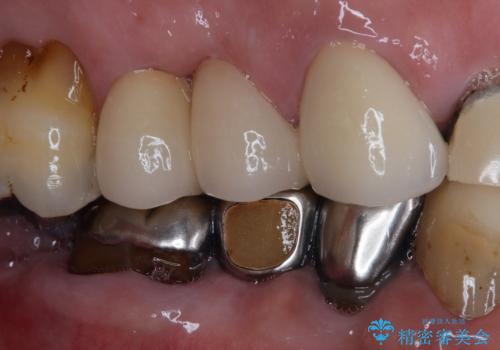

- 歯が割れてしまったとのことで来院された患者様です。

痛みは特にありませんでしたが、以前から歯が割れていることを指摘されており、徐々に不快感が増してきたとのことでした。

咬合力が強く、抜歯となる破折歯の前後の歯はいずれも神経が除去された歯であることから、ブリッジでは長期的な予後に不安があると判断されましたが、前後の銀歯も一気にきれいにしたいとのことで、オールセラミックブリッジによる補綴治療を行うこととしました。